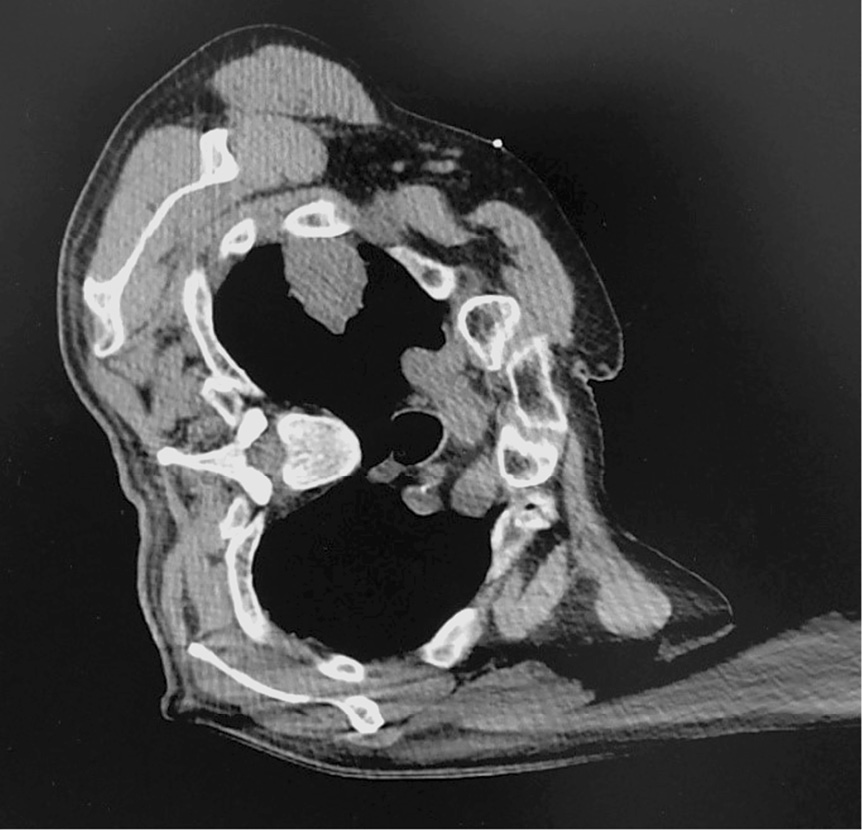

При втором (контрольном) сканировании определялась правильность расположения иглы у края опухоли, после чего игла заводилась в опухоль на несколько мм (рис. 4). После из коаксиальной системы удалялся стилет и в просвет устанавливалась биопсийная игла, выполнялось двукратное взятие биопсийного материала, после чего коаксиальная система удалялась. Полученный материал помещался в 10% раствор нейтрального формалина и передавался на морфологическое и иммуногистохимическое исследование (рис. 5).

Рис. 4. Компьютерная томограмма больного В. Конец коаксиальной системы локализован в стенке опухоли.